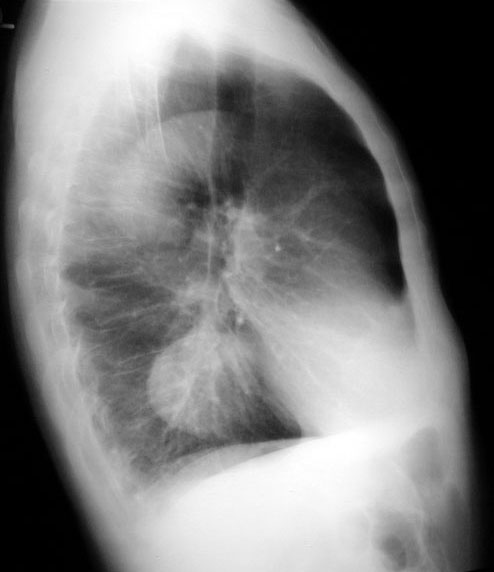

Inhomogeneous Cardiac Density / Double Density

The heart should be of uniform density, except over the vertebra and descending aorta. Left atrial enlargement can be recognized by the circular double density. Any time you see increased density in one portion compared to the rest of the heart, consider an abnormal density either in front of or behind the heart. Consider the following when you encounter inhomogeneous cardiac density:

This is an example of an aorta aneurysm.